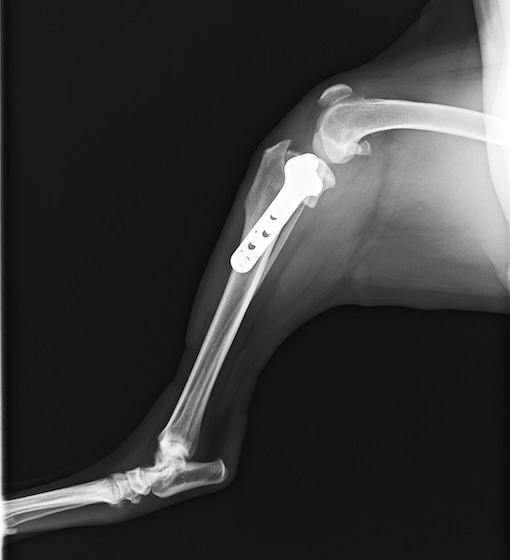

バーニーズマウンテンドック 4歳 避妊♀

突然の右後肢跛行を主訴に来院されました。整形外科学的検査において右膝に脛骨圧迫テストで陽性、前方引き出し徴候が認められました。神経学的検査において特に異常は認められませんでした。レントゲン検査において、関節液の貯留所見や脛骨の前方変位の所見が認められました。

関節鏡検査を実施いたしました。関節鏡検査では、重度の滑膜炎および前十字靭帯の完全断裂が認められました。半月板に損傷は認められませんでした。

断裂前十字靭帯の除去を行いました。その後 TTA(Tibial tuberosity advancement)を実施しました。

術後経過は良好で、後肢機能・筋肉量の改善目的で現在はリハビリテーションを行っています。